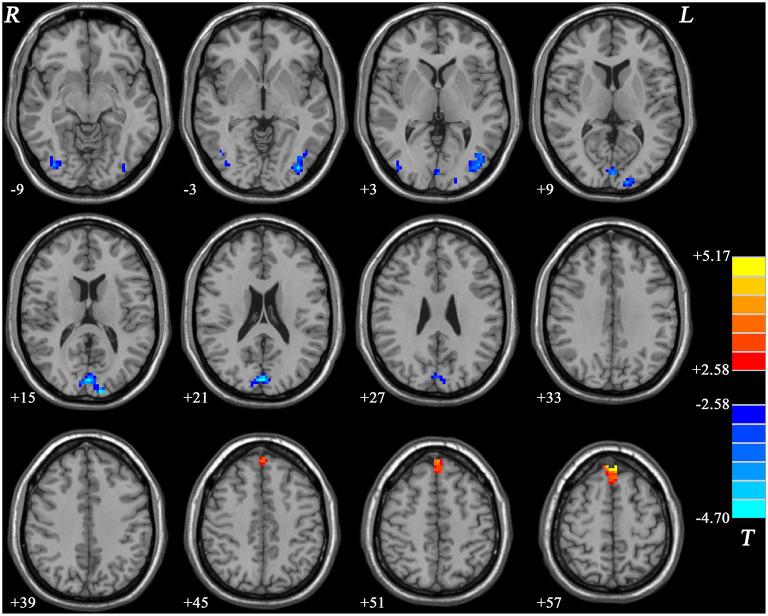

Gastrointestinal (GI) symptoms are fairly common somatic symptoms in depressed patients. The purpose of this study was to explore the influence of concomitant GI symptoms on the fractional amplitude of low-frequency fluctuation (fALFF) patterns in patients with major depressive disorder (MDD) and investigate the connection between aberrant fALFF and clinical characteristics. This study included 35 MDD patients with GI symptoms (GI-MDD patients), 17 MDD patients without GI symptoms (nGI-MDD patients), and 28 healthy controls (HCs). The fALFF method was used to analyze the resting-state functional magnetic resonance imaging data. Correlation analysis and pattern classification were employed to investigate the relationship of the fALFF patterns with the clinical characteristics of patients. GI-MDD patients exhibited higher scores in the HRSD-17 and suffered more severe insomnia, anxiety/somatization, and weight loss than nGI-MDD patients. GI-MDD patients showed higher fALFF in the right superior frontal gyrus (SFG)/middle frontal gyrus (MFG) and lower fALFF in the left superior medial prefrontal cortex (MPFC) compared with nGI-MDD patients. A combination of the fALFF values of these two clusters could be applied to discriminate GI-MDD patients from nGI-MDD patients, with accuracy, sensitivity, and specificity of 86.54, 94.29, and 70.59%, respectively. GI-MDD patients showed more severe depressive symptoms. Increased fALFF in the right SFG/MFG and decreased fALFF in the left superior MPFC might be distinctive neurobiological features of MDD patients with GI symptoms.

胃肠道(GI)症状是抑郁症患者中相当常见的躯体症状。本研究的目的是探讨伴发的GI症状对重度抑郁症(MDD)患者低频振幅分数(fALFF)模式的影响,并研究异常fALFF与临床特征之间的联系。本研究纳入了35例有GI症状的MDD患者(GI-MDD患者)、17例无GI症状的MDD患者(非GI-MDD患者)和28名健康对照者(HCs)。采用fALFF方法分析静息态功能磁共振成像数据。采用相关性分析和模式分类来研究fALFF模式与患者临床特征的关系。与非GI-MDD患者相比,GI-MDD患者在17项汉密尔顿抑郁量表(HRSD-17)上得分更高,且失眠、焦虑/躯体化和体重减轻更严重。与非GI-MDD患者相比,GI-MDD患者右侧额上回(SFG)/额中回(MFG)的fALFF更高,而左侧额内侧前额叶皮质(MPFC)的fALFF更低。这两个脑区簇的fALFF值组合可用于区分GI-MDD患者和非GI-MDD患者,准确率、敏感性和特异性分别为86.54%、94.29%和70.59%。GI-MDD患者表现出更严重的抑郁症状。右侧SFG/MFG的fALFF增加和左侧额内侧MPFC的fALFF降低可能是有GI症状的MDD患者独特的神经生物学特征。